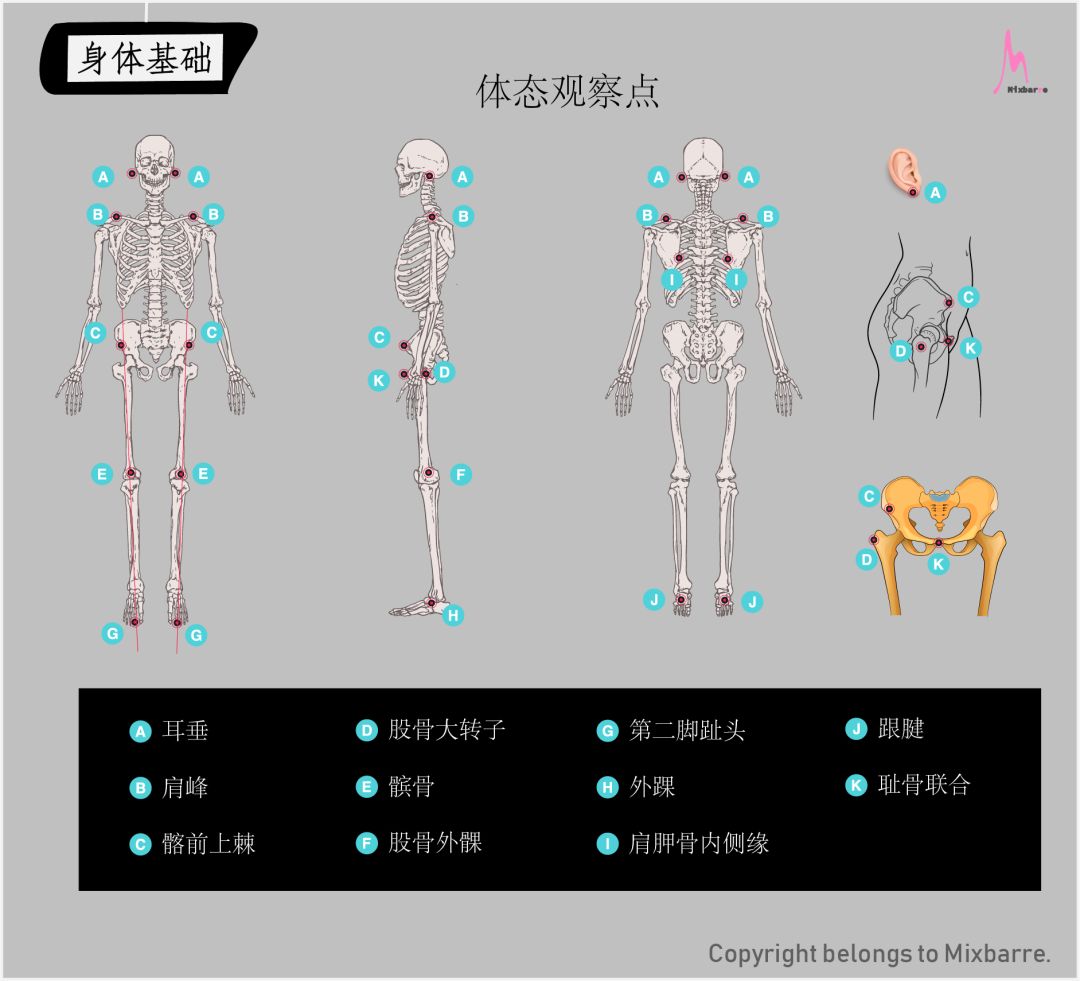

体态观察点

体态观察是通过几个关键的解剖点的排列来判断体态表现,常用的观察点请见下表。

注:上图中为了展示清楚,骨骼模型采用解剖学站姿,实际做体态观察时, 手臂 自然下垂即可。